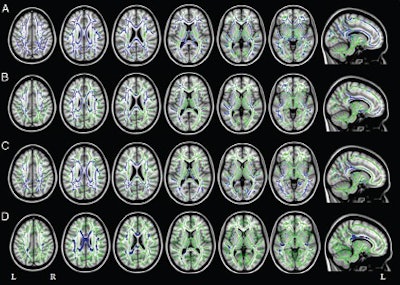

Filippi and colleagues used DTI to assess white-matter tracts in 28 patients with early-onset Alzheimer's, 12 with primary progressive aphasia, and 13 with posterior cortical atrophy. The 53 patients were matched in terms of age and gender with healthy control subjects for comparison purposes.

The researchers used a 3-tesla MRI scanner to perform 3D T1-weighted fast field-echo and DTI sequences on all subjects. DTI-MRI measures the movement of water molecules to characterize the microstructure of biological tissues and detect white-matter abnormalities.

All three groups of Alzheimer's patients showed a common pattern of white-matter damage in the corpus callosum, fornix, and main anterior-posterior pathways, as well as cortical atrophy of the left temporoparietal regions and precuneus, the researchers found.

In the two atypical Alzheimer's groups in particular, white-matter damage was worse and more widely spread than expected based on cortical atrophy. Filippi and colleagues suggested that the damage may spread through white-matter tracts from atrophied regions to previously unaffected cortical areas.

In the patients with primary progressive aphasia, fractional anisotropy decreased in certain regions of the brain's left hemisphere, as well as in a small area of the frontal white matter in the right hemisphere. Patients with posterior cortical atrophy showed a symmetrical pattern of fractional anisotropy decrease, as well as diffusivity increases in several brain regions.